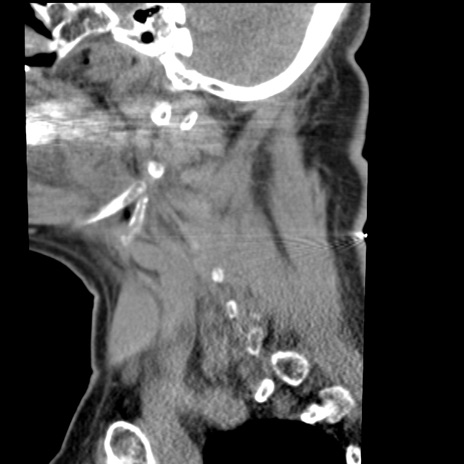

症例50 頚椎CT(矢状断像)

頚椎CT